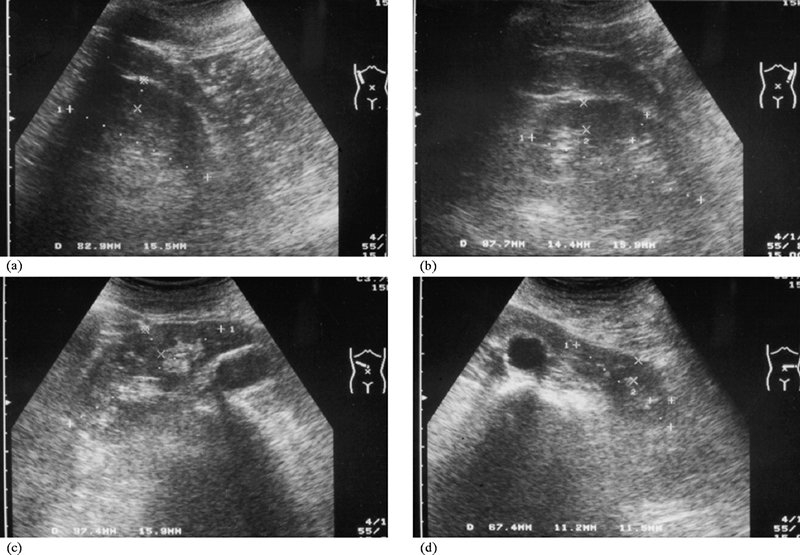

Siêu âm thận là kỹ thuật sử dụng sóng âm thanh để tạo ra hình ảnh về kích thước, cấu trúc hoặc đặc điểm bệnh lý của thận. Đây là một kỹ thuật có giá trị trong chẩn đoán các bệnh thận tại chỗ như sỏi thận, nang thận, áp xe thận, thận ứ nước hay suy thận. Siêu âm không xâm lấn, không đau, an toàn cho bệnh nhân và rất chính xác.

Những đặc điểm gợi ý khi khám siêu âm toàn thận bình thường: Thận hình pha, dốc nằm vào trong, kích thước hai thận thường không giống nhau, dài khoảng 9 - 12 cm, rộng 4 - 6 cm và dày khoảng 3 - 4 cm, mép nhẵn, nhu mô thận trái hình tam giác (do tỳ đè từ bên trái vào). Siêu âm không thể nhìn thấy niệu quản ở người khỏe mạnh. Nếu niệu quản lộ ra ngoài thường là do dị dạng niệu quản hoặc niệu quản bị giãn rộng. Các động mạch và tĩnh mạch thận cũng có thể nhìn thấy rõ ràng khi kiểm tra siêu âm.

Siêu âm có biết bị suy thận không? Trên thực tế, siêu âm cho kết quả không thuyết phục trong các bệnh thận lan tỏa như viêm cầu thận cấp, viêm cầu thận mãn tính, hội chứng thận hư và amyloidosis thận. Tuy nhiên, nếu bệnh chuyển sang giai đoạn suy thận, ảnh hưởng nghiêm trọng đến kích thước của thận thì việc siêu âm sẽ cho kết quả rõ ràng. Vì khi đó kích thước của thận nhỏ hơn bình thường.

Vì vậy, có thể thấy suy thận có thể được phát hiện trên siêu âm lâm sàng. Tuy nhiên, để chẩn đoán chính xác và nâng cao hiệu quả điều trị, cần phải thực hiện nhiều lần siêu âm.

Siêu âm đánh giá tình trạng suy thận như thế nào?

Siêu âm là một phương pháp hình ảnh được sử dụng để đánh giá suy thận cấp tính hoặc mãn tính, đôi khi được bổ sung với siêu âm Doppler. Trên thực tế, hầu hết các trường hợp suy thận đều không rõ nguyên nhân, do đó, siêu âm có thể giúp xác định một số nguyên nhân gây suy thận và từ đó đưa ra phương pháp điều trị thích hợp. Các vấn đề thường gặp gây suy thận có thể được phát hiện qua siêu âm bao gồm:

• Suy thận giai đoạn cuối: Nếu hai quả thận dài dưới 6 cm được coi là bệnh thận giai đoạn cuối. Hiện tại, vỏ thận không đủ ổn định để duy trì chức năng tự nhiên, bệnh nhân bị suy thận nặng. Hình ảnh siêu âm cho thấy cơ thể bị teo kích thước, tủy thận bị giảm phản xạ, tủy thận bị mất.

Trong trường hợp thận vẫn có kích thước bình thường và không bị viêm bể thận, siêu âm không đủ để khẳng định chẩn đoán mà chỉ đưa ra một số khuyến cáo. Ở những bệnh nhân có kích thước thận bình thường và không có vách ngăn thận mở rộng, cần làm thêm thủ thuật sinh thiết thận để đảm bảo chẩn đoán chính xác suy thận. Sinh thiết được thực hiện tốt dưới hướng dẫn của siêu âm.